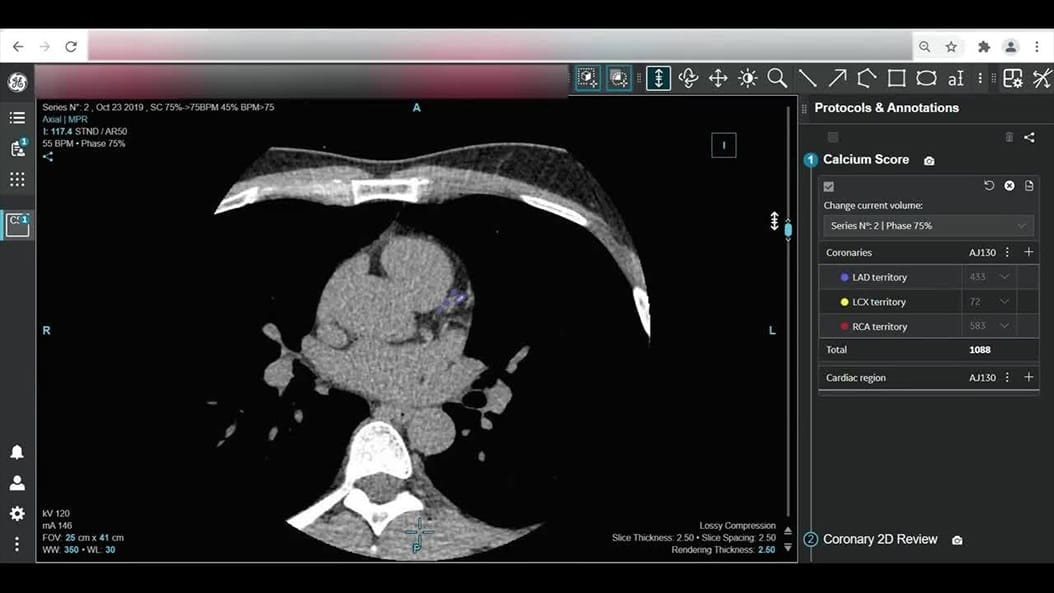

CardiQ Suite

An integrated suite of CT Cardiac post-processing tools, built for automation and workflow efficiency.

Consistency

>90% concordance with CACS‑DRS classification grouping⁵

Identification

>95% correct identification of the presence of coronary artery calcifications⁵

Labeling

>90% accurately labeled coronary artery territories⁵